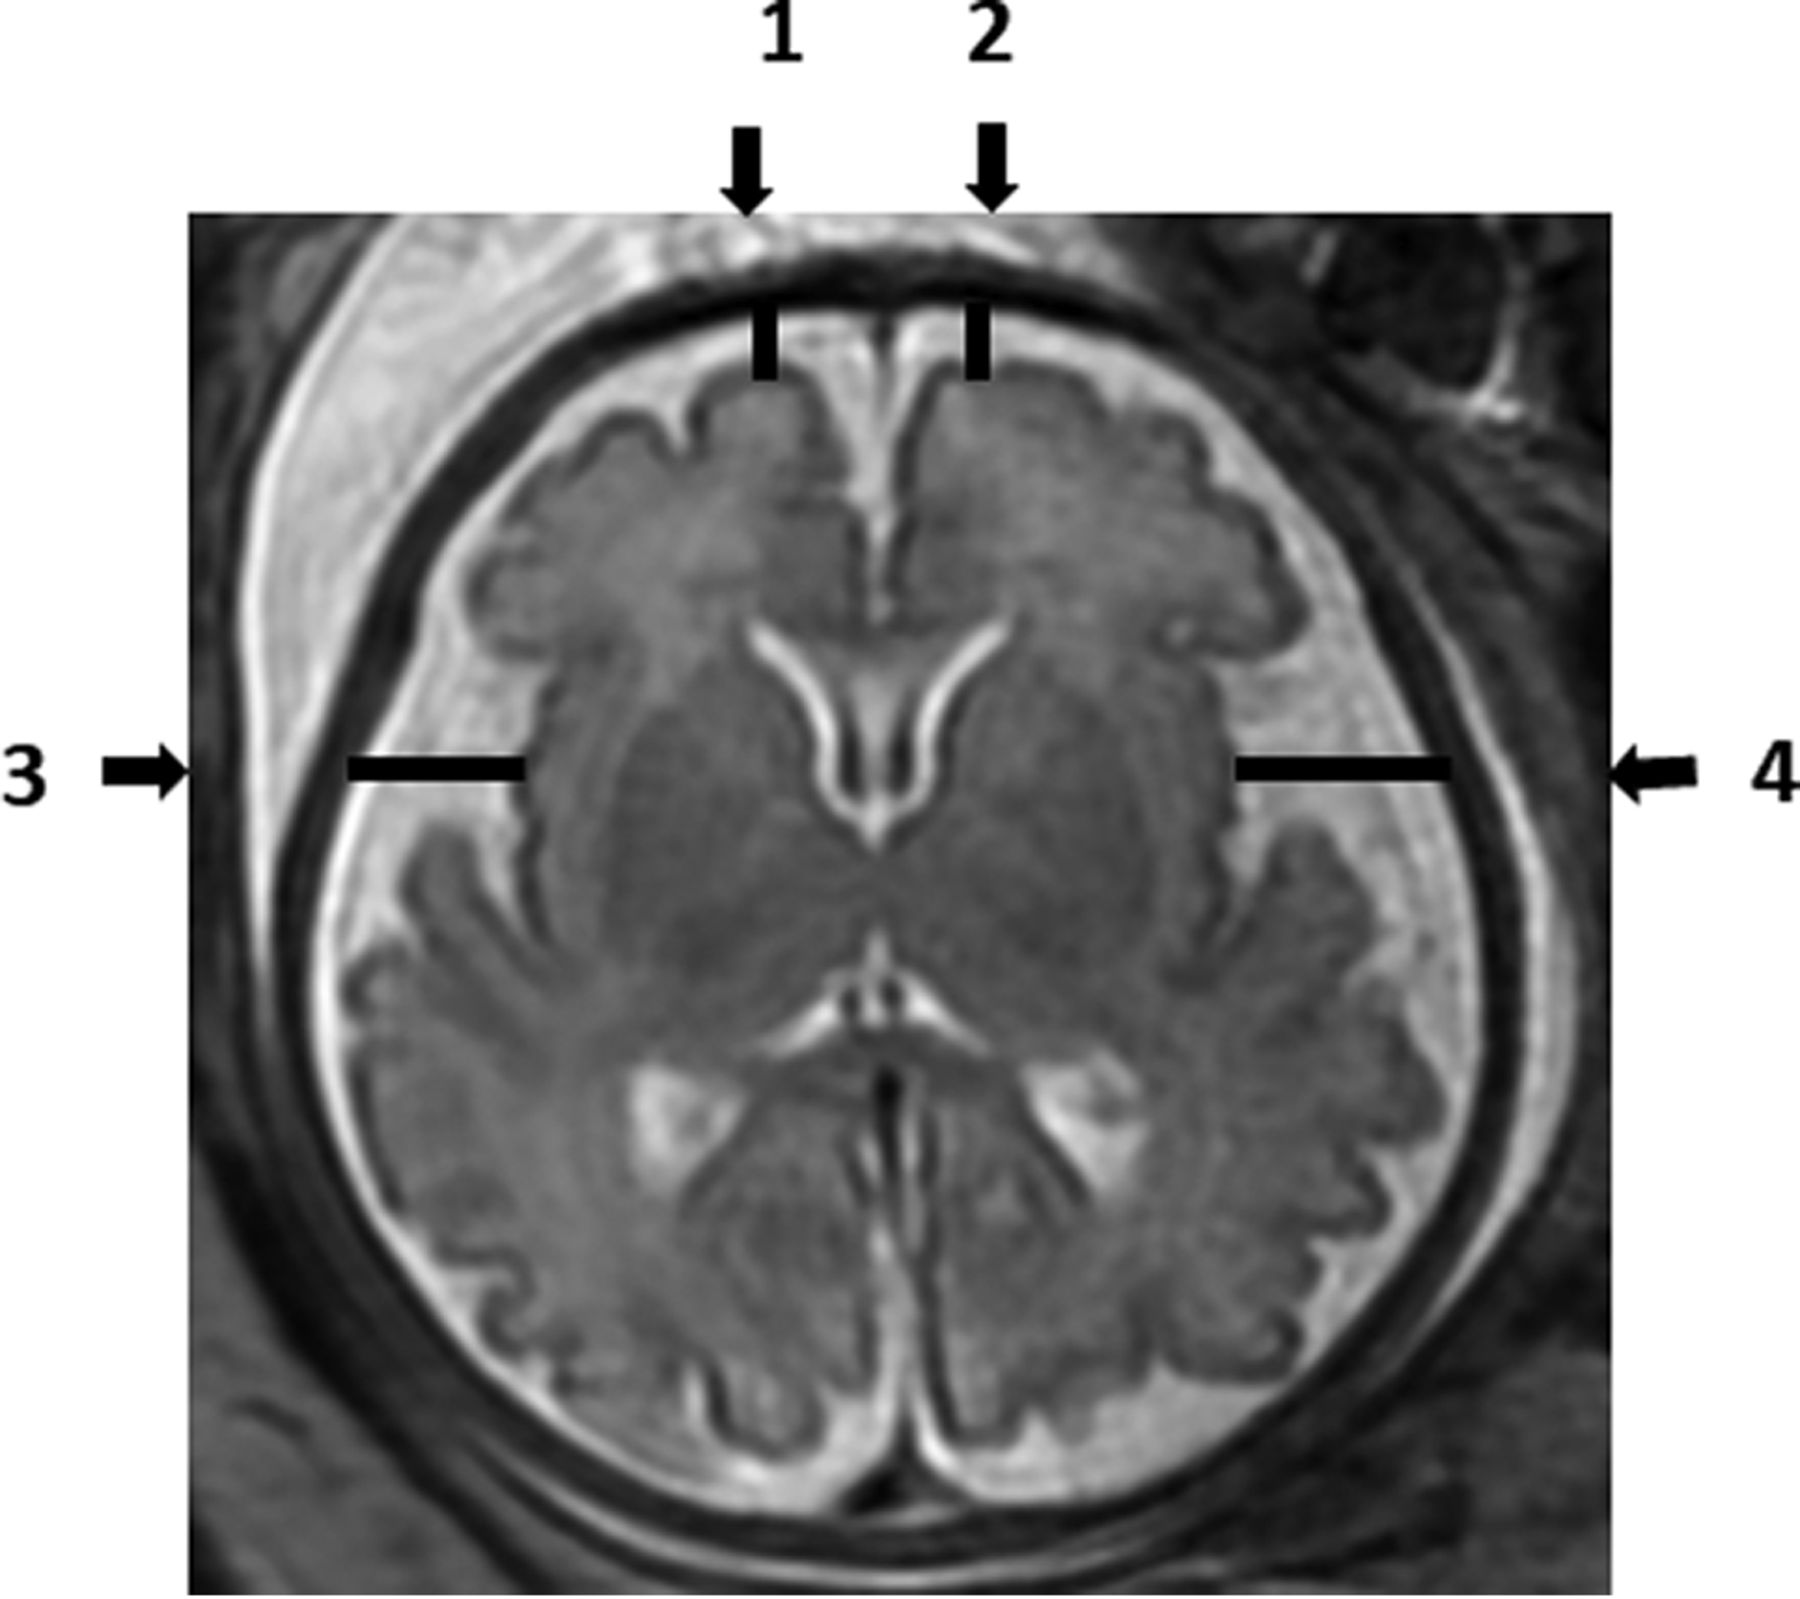

Each MR imaging examination was routinely read by 2 expert physicians to detect any abnormality. Measurements of the SAS size, which was identified by a high signal (white color) at T2-weighted imaging, were analyzed manually by a single reader (A.W.) on the PACS reading workstation. Measurements were recorded in 2D slices. The SAS was measured in millimeters, in 4 locations of the axial section (Fig 1), and in 6 locations of the coronal section (Fig 2). All measurements were obtained at the level of midinsula from the cortex to the internal margin of the cranium as shown in Figs 1 and 2: axial section - right frontal gyrus, left frontal gyrus, right insula gyrus, left insula gyrus; coronal section - right frontal gyrus, left frontal gyrus, right insula gyrus, left insula gyrus, right inferior temporal gyrus, and left inferior temporal gyrus.

Coronal T2-weighted fetal brain image demonstrating the measurements of the subarachnoid space: 1) Right frontal gyrus. 2) Left frontal gyrus. 3) Right insula gyrus. 4) Left insula gyrus. 5) Right inferior temporal gyrus. 6) Left inferior temporal gyrus.